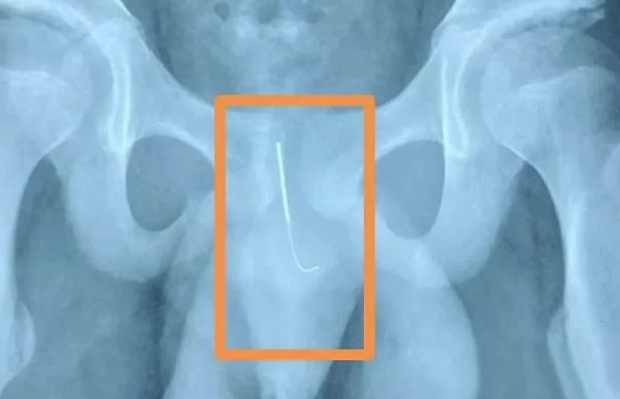

病院で治療を受ける前にレントゲン撮影をしたシャオロン。

するととんでもない結果が明らかに…。

なんと、シャオロンの陰茎に約10cm程度の針が挿入されていることが確認されたのです。

シャオロンは夜中に徹夜で宿題をしている最中、あまりにも眠くなったため、世紀に針を挿入するなどの刺激を与えて、眠気を飛ばしていたといいます。その過程で、針がすべて入り込んでしまったといいます。